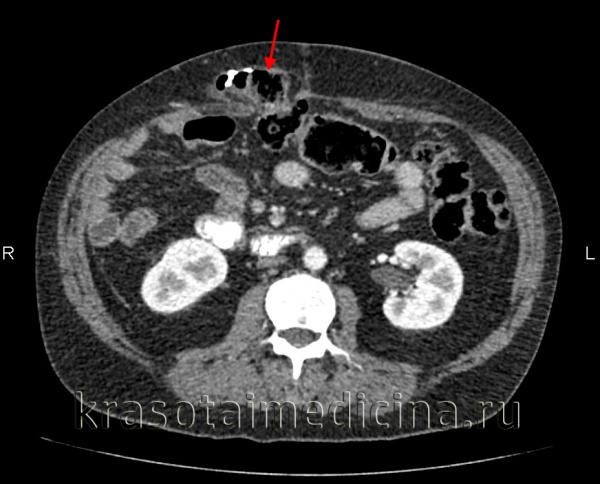

(Слева) На аксиальной КТ с контрастным усилением у пациента после наложения обходного анастомоза желудка определяется дилятация «малого желудка», отводящей петли, проксимальных отделов тонкой кишки, а также резкое сужение дистальных отделов тонкой кишки и ободочной кишки.

(Справа) На аксиальной КТ с контрастным усилением у этого же пациента отчетливо определяется «скручивание» корня брыжейки тонкой кишки, полнокровие брыжеечных вен, по которым осуществляется отток крови из сегментов кишки, находящихся в грыже, подвергшихся обструкции. Эти изменения обусловлены чрезбрыжеечной внутренней грыжей и заворотом кишки.

(Слева) На аксиальной КТ с контрастом у пациента с болью в животе после тотальной колэкто-мии (по причине язвенного колита) визуализируется грыжевое выпячивание тонкой кишки через дефект в брыжейке сигмовидной кишки, а также скручивание сосудов брыжейки в области грыжи.

(Справа) На аксиальной КТ с контрастным усилением, выполненной пациенту с выраженной болью и снижением системного давления, определяется признак «водоворота», который заключается в «скручивании» проксимальных отделов тонкой кишки и брыжеечных сосудов вокруг своей оси. При хирургическом вмешательстве было обнаружено грыжевое выпячивание тонкой кишки в дефект брыжейки.